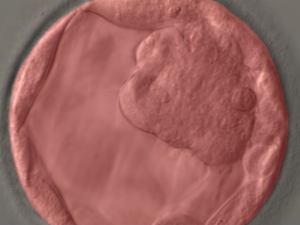

The system is powered by AI models that perform classification, detection and segmentation on the images. Segmentation of blastocoel cavity, trophectoderm and ICM computation on day 5 images is conducted. Thereafter, IVF embryo gradings are performed that are based on Istanbul concensus. All the images are stored in a central repository for AI model training.

KritiLife platform will grade the embryos on the basis of their development and respective images captured on day 5 as per pre-defined criteria. This aids embryologists in gaining a second opinion to select embryos that possess the best potential for viable implantation.